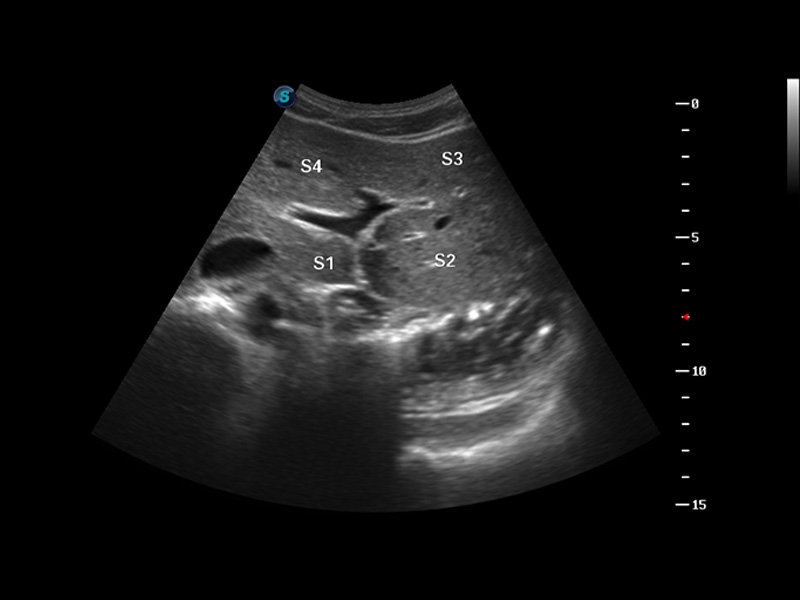

S8 EXP便携式彩色多普勒超声诊断仪是美狮贵宾会官网研发的高端全身应用型便携彩超。高通道的VIS平台融合可视化(Visual)、智能化(Intelligent)和人性化(Smart)的特点,配以美狮贵宾会官网自主研发生产的探头大家族,使您能够快速、准确的获得病人信息,提高工作效率的同时减轻疲劳。